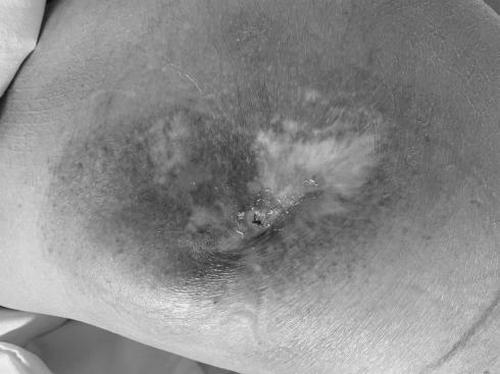

▲ 右髋部

创面评估均为Ⅳ期压疮,治疗难度大,周期长,与患者家属充分沟通病情,取得家属信任。两位治疗师先通过溶痂及清创的方式去除表面痂皮,暴露皮下坏死组织,探查可见均合并较深的窦道和腔隙,如此大面积的压疮,自行愈合非常困难,多次建议患者家属创面稳定后行手术治疗,考虑到手术及麻醉风险,家属坚持保守换药治疗,给两位治疗师增加了不少难度,早期每次换药时间都在半小时左右。蚕食清创的同时配合银离子、负压、生长因子、泡沫敷料等方式,创面逐渐好转。同时也给护理提出了非常高的要求,施敏护士长亲自指导,制定护理方案,使用气垫床,每2小时翻身1次,减压保护创面的同时也要预防新发压疮的形成;翻身拍背等预防肺部感染,踝泵运动预防下肢深静脉血栓形成。